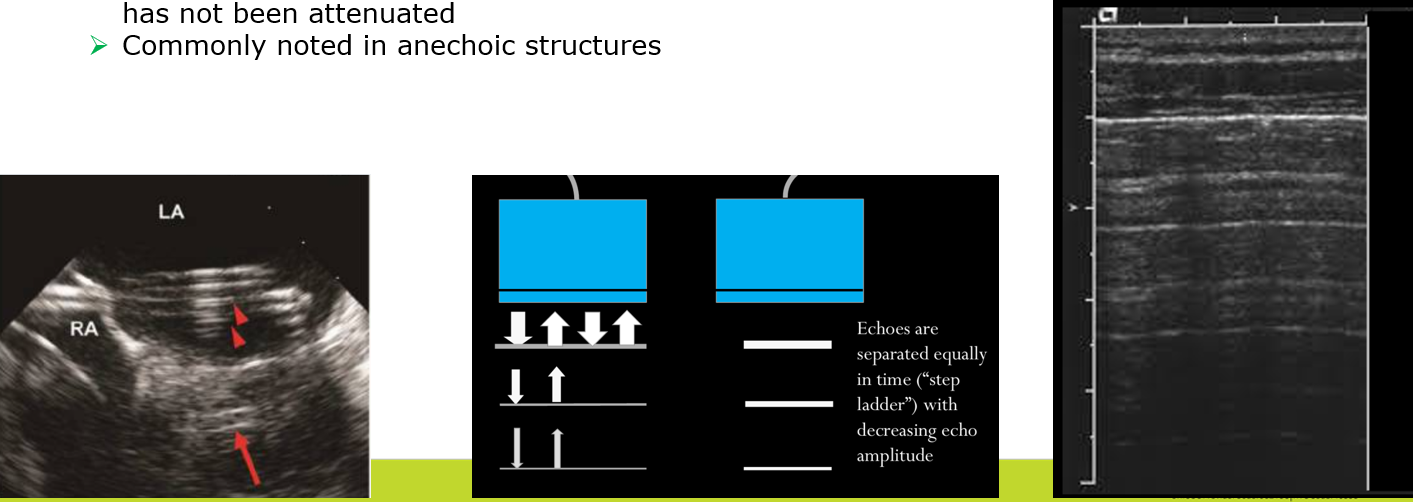

Reverberation Artifacts

Tissues are displayed multiple times at equally spaced depths due to repeated reflections.

Only the first reflection is spatially correct.

Characteristics:

Parallel to the sound beam’s main axis.

Decreasing in intensity.

Equidistant from each other.

Echoes can appear between the transducer and a strong reflector or between two strong reflectors.

Simple Reverberation Artifact

Sound bounces between the transducer and a strong specular reflector, or between two strong specular reflectors.

Ringdown Artifact

Reflectors are gas bubbles.

Multiple echoes are seen due to sound reverberating back and forth between air/soft tissue interfaces and within gas bubbles.

Strong, bright, repeating lines are observed deep to gas bubbles.